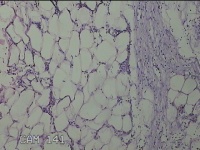

右侧腋下结节

性别

男

年龄

56岁

临床诊断

一般病史

标本名称

大体所见

灰白粉红色组织2.3x2x0.8cm一块,表面带梭形皮肤2.3x2cm,皮下见结节2x1cm一个,结节部分已切开,见结节呈囊性,囊内有少许灰白色角化物,囊壁厚0.1cm。

炎性病变。